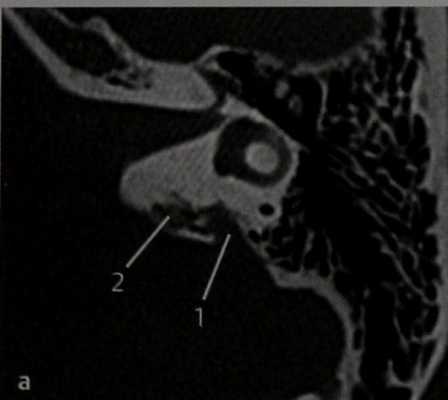

КТ в горизонтальной проекции. Видна деструкция заднемедиального отдела височной кости в области предполагаемого расположения эндолимфатического мешка, по-видимому, обусловленная его опухолью. Водопровод преддверия при этой опухоли может быть расширен (1), и в большинстве случаев опухоль прорастает в окружающую ее кость (2), распространяясь на луковицу ВЯВ, внутренний слуховой проход, сосцевидный отросток, внутреннее ухо. Поражение интракраниальных структур лучше видно на МРТ.